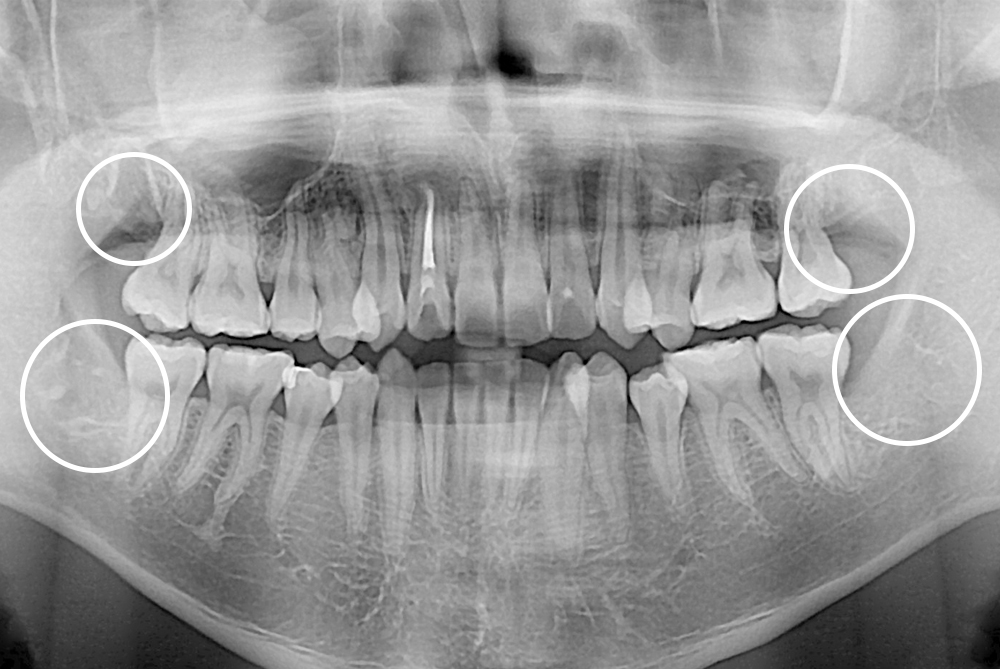

[사랑니] 매복 사랑니 발치

치료후 : 2021-02-06

세종치과는 구강악안면외과학 박사이신 원장님이 발치하는 치과입니다.